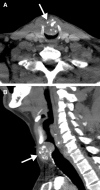

Primary dedifferentiated chondrosarcoma occurring in the larynx is a rare head and neck malignancy. The cases reported in the literature suggest male gender predilection and variable clinical outcomes ranging from disease-free survival to disease-related death. Although a calcified matrix is suggestive of chondrosarcoma, the dedifferentiated component is not readily appreciated on conventional imaging modalities and thorough tissue sampling is necessary for confirming the diagnosis. Histologically, there is an abrupt transition from a well-differentiated chondrosarcoma to a high-grade spindle cell component, which can show focal heterologous differentiation. These features are exemplified in this sine qua non radiology-pathology correlation article.